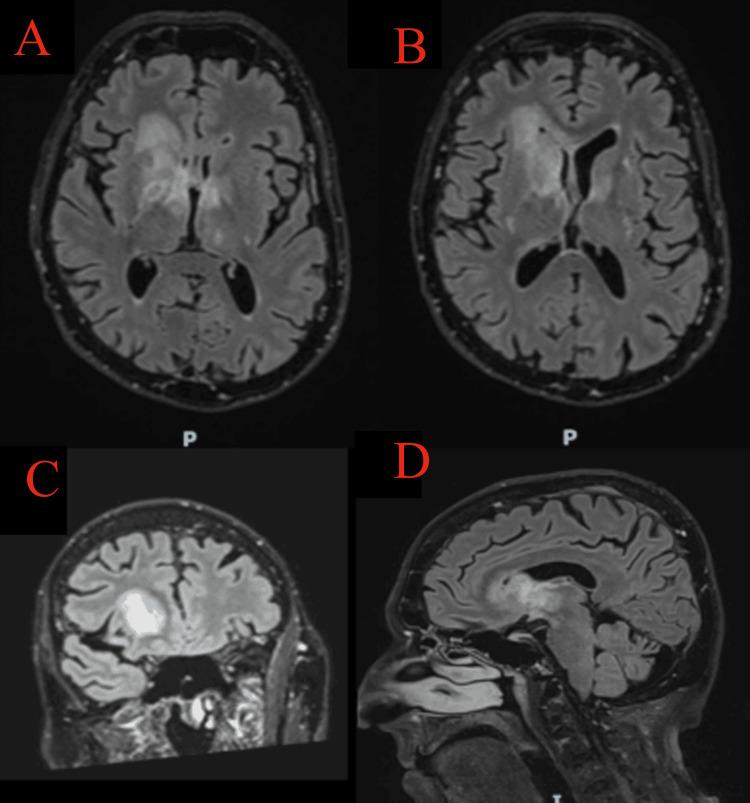

Cognitive impairment in the elderly is often attributed to neurodegenerative processes such as dementia or delirium. However, in some cases, structural brain lesions, including malignancies like glioblastoma and lymphomas, can present similarly. This case report is of a 79-year-old male with progressive cognitive decline who was initially suspected to have dementia but was later found to have a brain mass. The absence of focal neurological deficits and a normal initial CT scan delayed the recognition of an underlying malignancy. An MRI ultimately revealed a lesion concerning glioblastoma or primary central nervous system lymphoma (PCNSL). Given the patient's frailty, the neuro-oncology multidisciplinary team (MDT) recommended best supportive care rather than an invasive biopsy. This case underscores the importance of thorough assessment and neuroimaging in cases of unexplained cognitive decline and highlights the diagnostic pitfalls that can lead to misdiagnosis.

老年人的认知障碍通常归因于神经退行性过程,如痴呆或谵妄。然而,在某些情况下,包括胶质母细胞瘤和淋巴瘤等恶性肿瘤在内的脑结构病变也可能表现出类似症状。本病例报告的是一名79岁男性,其认知功能进行性下降,最初被怀疑患有痴呆,但后来发现有脑肿块。由于缺乏局灶性神经功能缺损且初始CT扫描正常,导致对潜在恶性肿瘤的识别延迟。最终MRI显示出一个可疑的胶质母细胞瘤或原发性中枢神经系统淋巴瘤(PCNSL)病变。鉴于患者身体虚弱,神经肿瘤多学科团队(MDT)建议采取最佳支持治疗,而非进行侵入性活检。该病例强调了在不明原因认知下降病例中进行全面评估和神经影像学检查的重要性,并突出了可能导致误诊的诊断陷阱。